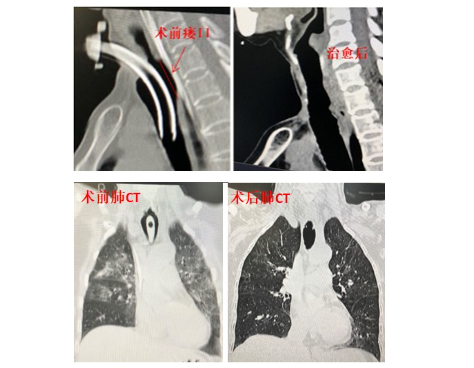

6月6日,患者家属得知湘雅三医院耳鼻咽喉科综合实力强,抱着最后一线希望,带着所有资料找到了谭国林教授会诊,谭教授仔细阅评所有医疗资料后,给出了意见:(1)气管食管瘘导致的吸入性肺炎非常严重,整个肺部几乎是“白肺”,这是致命的;(2)气管食管瘘巨大,涉及到了颈、胸两个解剖区域,治疗难度大,气管支架或者食管支架不可能解决问题,但认为患者还是有希望通过手术治愈的。家属遂将患者从外院ICU通过120直接转入了头颈外科病房,先进行了精准的气道管理和专业的营养治疗,并实施了多次全科疑难病例讨论及多学科会诊。病情稍有好转后,在麻醉科实施个性化麻醉下,采用颈部切口,达到气管食管瘘上方,内镜检查发现漏口有6.5厘米长,下方接近气管隆突,上方接近环状软骨,手术操作难度大,需要麻醉科反复拔除麻醉气管导管才能操作,在内镜下精准切除气管食管瘘的漏口边缘,将气管与食管完全分离,然后分层缝合食管,制作10厘米长的颈部带血管蒂皮瓣修复整个气管后壁及侧壁;并将喉临时旷置,气管外提,以阻止经喉部的误吸。术后经过抗感染,鼻饲胃肠营养、肠外营养治疗及支气管灌洗等治疗,患者的感染指标逐渐好转,咳嗽咳痰越来越少,术后20天的影像资料显示气管食管瘘消失,肺部感染明显好转,遂转到康复医院继续进行吞咽康复训练。术后50天,患者返回科室再次手术,将旷置的喉和外提的气管接回原来的解剖部位,回家继续进行吞咽训练,并指导其发音训练,术后3个月再次来医院拔除了气管导管,封闭了颈部的气管切开造口。此次例行的复查结果显示,患者的吞咽、呼吸、发音功能基本恢复正常,肺部遗留一些纤维化外,肺部感染完全消退。